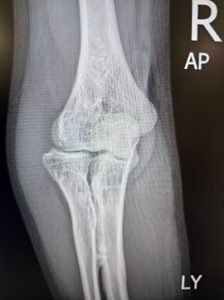

An X-ray is required to confirm the fracture and assess displacement of the bone. Sometimes, Dr Bala might suggest a CT scan may also be needed to obtain further details of the fracture, especially the joint surfaces. Dr Bala might inject local anaesthesia into the joint and check for a block to forearm rotation movements to decide on the need for surgery. He may also ask for x-rays of the entire forearm or of the wrist of the same side to rule out associated injuries.